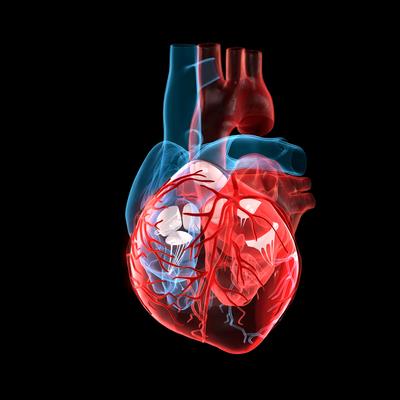

Inflammatory Cardiomyopathy: From Pathogenesis To Precision Therapy